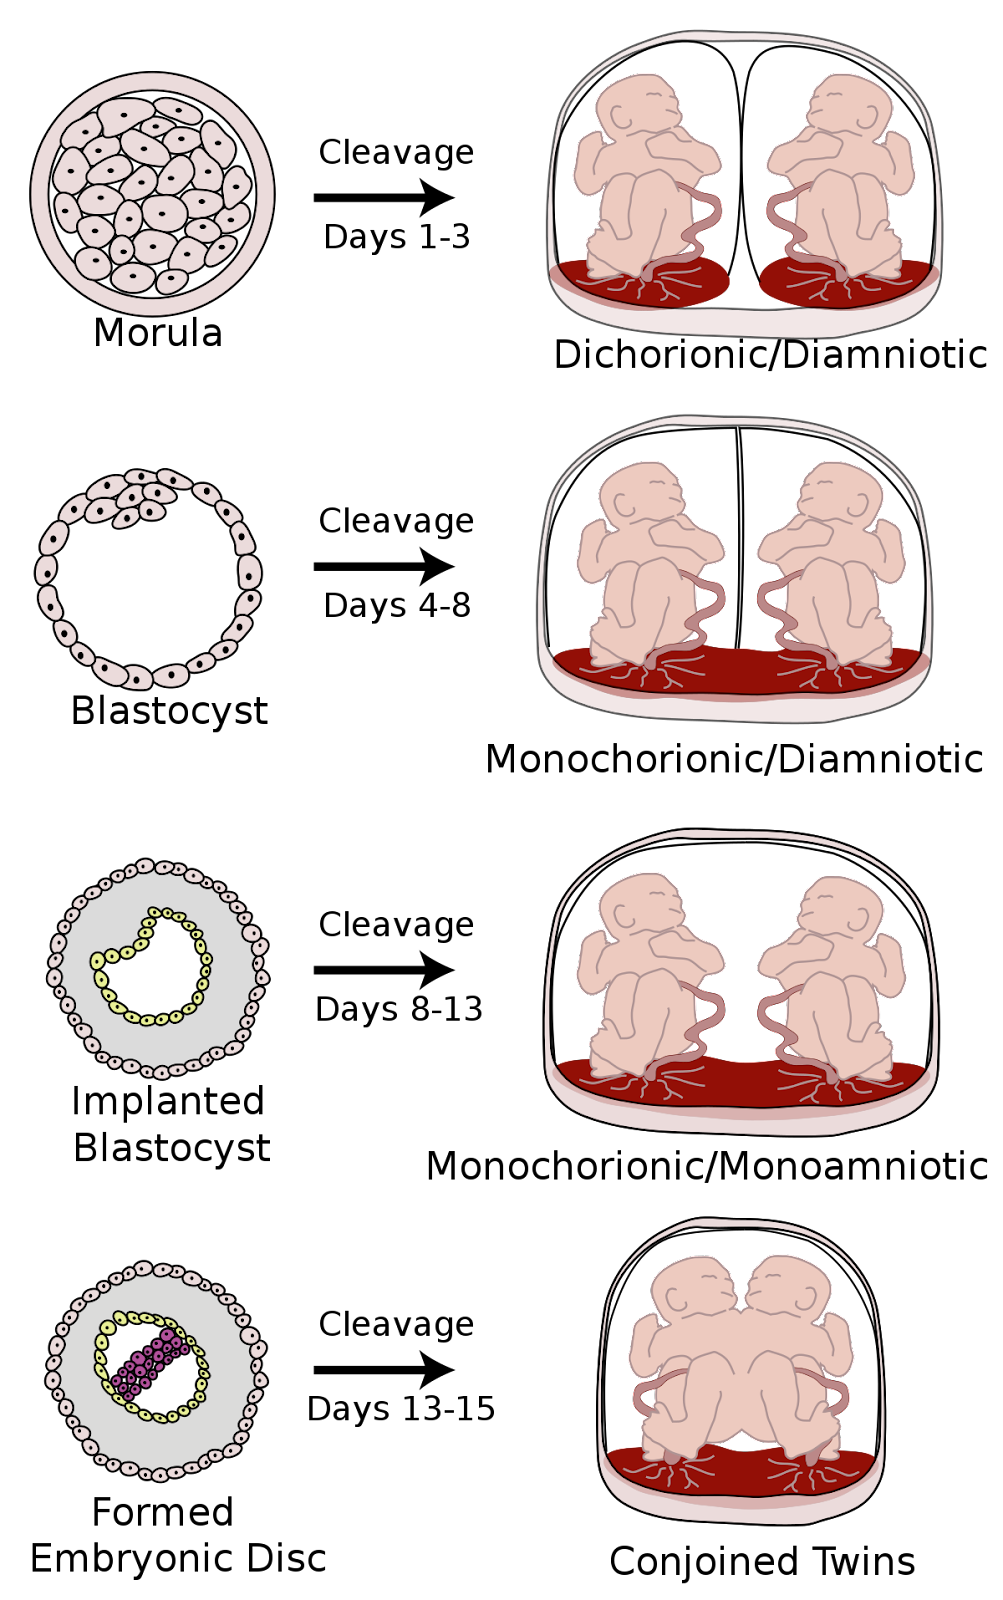

Comparison of monozygotic vs. dizygotic twins Identical twins (monozygotic twins) Fraternal twins (dizygotic twins) Frequency ⅓ of all twin pregnancies ⅔ of all twin pregnancies Origin Division of the fertilized oocyte into two embryonic layers Fertilization of two oocytes with two mature spermatozoa Genetics of the individual Genetically identical Genetically different Chorionic cavity and amniotic sac Varies Dichorionic-diamniotic - Development Variations in Monozygotic Twins: The timing of the zygotic division significantly affects chorionicity and amnionicity, ranging from dichorionic-diamniotic to monochorionic-monoamniotic, with the latter including the rare occurrence of conjoined twins.

- Ultrasound: Essential for identifying multiple fetuses and determining chorionicity and amnionicity, with specific signs indicating dichorionic or monochorionic twins.

- Differentiating Twin Types Early On :

- Dichorionic Twins:

- Lambda Sign: Indicates twins with separate chorionic and amniotic sacs, seen as a λ-shaped separation on ultrasound.

- Monochorionic Twins:

- T-Sign: Suggests twins share a chorionic sac but have individual amniotic sacs, appearing as a T-shaped separation on ultrasound